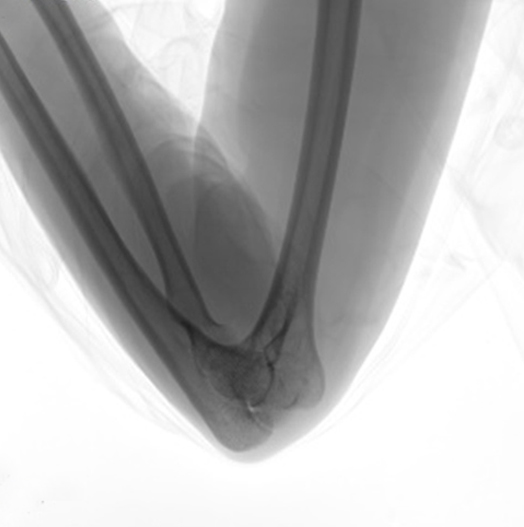

長年の経験により蓄積されたノウハウで卓越した診断映像を提供します。